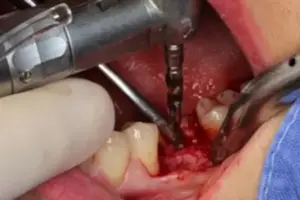

März: 8 Wochen später: Herr F. hat seinen Termin zur Implantation bei mir in der Praxis. Vor dem Eingriff habe ich bereits, anhand von Röntgenaufnahmen, überprüft, ob der vorhandene Knochen breit und tief genug ist, um ein Implantat bestimmter Länge und Durchmessers zu setzen. Siehe Bild 2.

Dies ist bei Herrn F der Fall. Somit erhält Herr F. eine kleine örtliche Betäubung, genau wie damals als der Zahn entfernt worden ist. Die örtliche Betäubung stellt sicher, dass Sie als Patient während meines Eingriffs absolut schmerzfrei bleiben. Hierüber müssen Sie sich somit keine Gedanken machen – und ich mir auch nicht. So kann ich mich zu 100% auf die professionelle Einsetzung Ihres Zahnimplantats konzentrieren.

Bild 2: Zahnlücke von fehlendem Zahn 36

Dort, wo das Implantat gesetzt werden soll, wird das Zahnfleisch etwas zur Seite geschoben, damit ich eine gute Sicht auf den Knochen erhalte. Siehe Bild 3.

Bild 3: Zahnfleisch wird zur Seite geschoben

Anschließend bereite ich das Implantat-Bett von Herrn F. mit verschiedenen kleinen Bohrern auf, in welches der Implantat-Körper danach eingebracht wird.